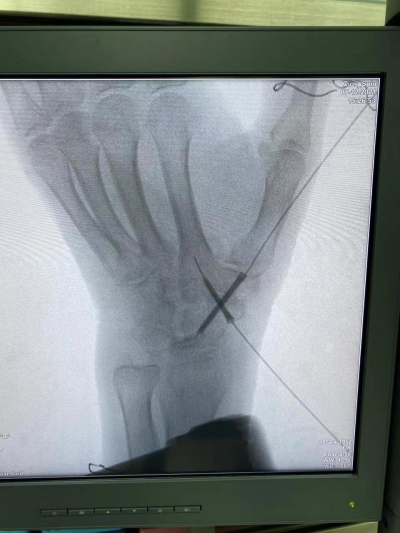

近日,手足显微外科中心郝增涛教授团队再次完成一例“天玑Ⅱ”骨科手术机器人导航下精准定位经皮内固定舟骨骨折桡骨远端骨折,在机器人的帮助下做到了置钉角度和位置最佳,既缩短了手术时间,又减小患者创口,同时又缩短了医生在X线下操作的时间,最大程度地保护了医生和患者。

据郝增涛主任介绍,由于腕舟骨体积小、解剖结构复杂,螺钉置入位置欠佳,会引起骨折处稳定性不良,还有愈合时间长。而有了骨科手术机器人参与手术,精准导航,螺钉可一次性成功置入,减轻了手术风险,使患者受益良多。“天玑Ⅱ”骨科手术机器人可谓是一个好帮手、好伙伴。

利用“天玑Ⅱ”骨科手术机器人技术,大幅缩短了手术时间,减小切口长度,显著减少了患者术中及术后的并发症发生率,使得术后住院时间、术后康复周期较以前明显缩短,患者的综合手术费用明显降低,真正做到了使复杂手术更加安全,常规手术微创化,发挥“智能+人工”的最大效益。